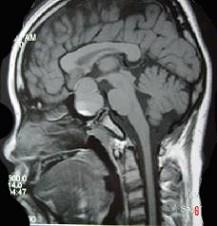

问题 男,47岁,视物模糊数月,头痛、恶心、呕吐3天,行MRI检查如图,最可能的诊断为()

选项 A.颅咽管瘤 B.脑膜瘤 C.蛛网膜囊肿 D.垂体瘤并出血 E.表皮样囊肿

答案 D